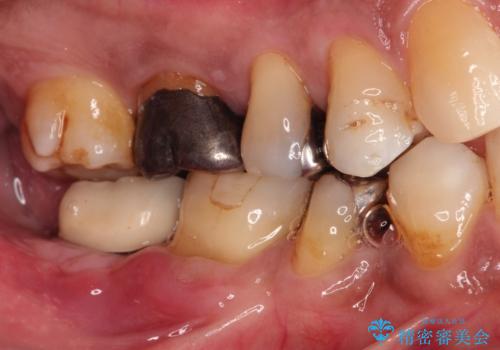

- 奥歯が痛いことを主訴に来院されました。

重度の歯周病により保存困難と診断し、抜歯後にインプラント治療を行いました。

抜歯後十分な骨の回復が認められず、単独の骨増生を行った後にインプラントを埋入しました。